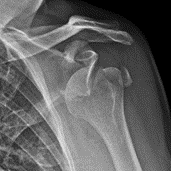

X-ray of Anterior Dislocation of Shoulder

An X-ray showing a simple anterior dislocation of the shoulder, meaning the shoulder slid forward out of the socket.